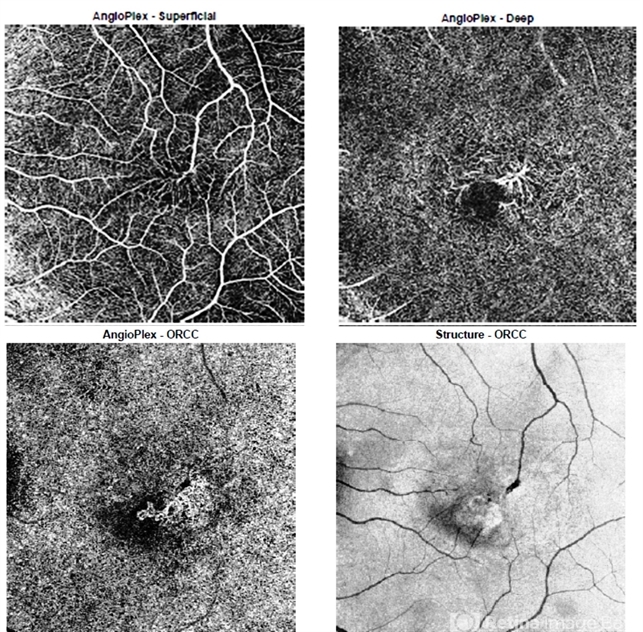

- Mac Tel type 2

- Optical coherence tomography angiography allows for 3-dimensional vessel imaging and may help detect abnormal vessels earlier than fluorescein angiography, which was historically used in diagnosis of MacTel type 2. This OCTA of the left eye of a 52-year-old male captures superficial telangiectatic macular vessels (top left) and follows them as they dive into deeper capillary layers (top right). The structural image of this OCTA (bottom right) shows the classic “right angles” of these abnormal vessels as they plunge. The outer retinal slab image (bottom left) shows a choroidal neovascular membrane, which is a rare complication of MacTel type 2.